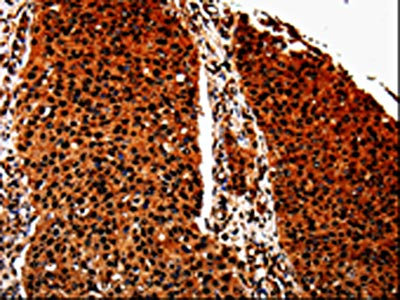

The image is immunohistochemistry of paraffin-embedded Human lung cancer tissue using CSB-PA196764(ANXA7 Antibody) at dilution 1/40. (Original magnification: ×200)

The image is immunohistochemistry of paraffin-embedded Human renal cancer tissue using CSB-PA196764(ANXA7 Antibody) at dilution 1/40. (Original magnification: ×200)